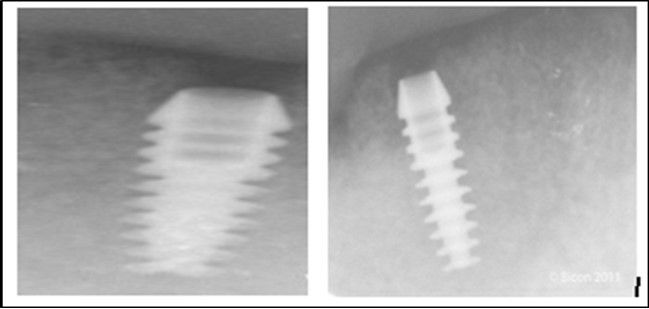

Post operatively after 3 months, osseointegration was evaluated clinically and radiographically (Figure 5a,b) and the implants were well prepared to receive the prosthesis. The second stage surgery was performed in which cover screws were removed and healing abutment were inserted into the implants (Figure 6). After a time period of two weeks, peri-implant soft tissue healing was examined, and existing denture was relined after relieving at the abutment site. Later, the healing abutment is removed using a 1.25 mm hex driver. Internal portion of the implant is irrigated and dried to make sure if it is free of debris and soft tissue. A periodontal probe was used to measure the gingival cuff height at the right and left canine site of implant location. Selected ball abutment were placed onto each implant using 1.25 mm hex driver and 30 Ncm torque wrench (Figure 7A).

Figure 5.a,b. Post-insertion radiographics in the mandibular area right,left,

Figure 6.Panoramic radiograph after the insertion of two implants